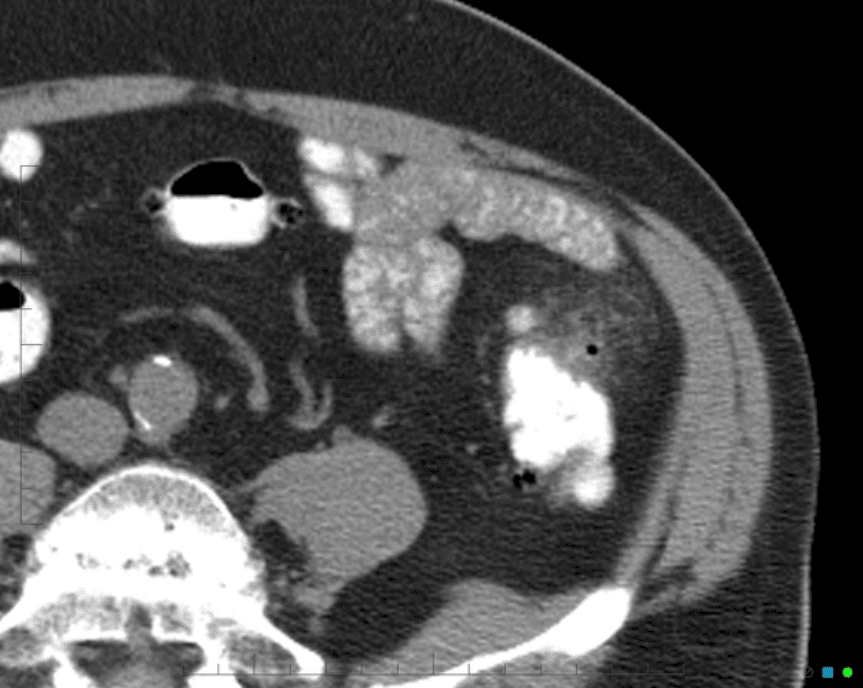

Viêm túi thừa

Viêm túi thừa - Ảnh 4

» Thông tin: Nam giới – 25 tuổi.

» Lâm sàng: Đau hố chậu trái.